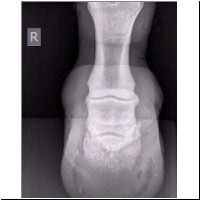

Eselstute "Peggy" zeigte eine hochgradige Lahmheit des rechten Vorderhufes. Der Huf wurde NICHT genutzt. Die erste Untersuchung zeigte, dass es kein Hufgeschwür, Rehe oder ähnliches war. Darauf hin machte der Tierarzt Röntgenbilder.

rechter Vorderhuf, von der Seite

Zu sehen ist der rechte Voderhuf von der Seite - ohne sichtbare Veränderungen.

Hufbein, Strahlbein, Kronbein u. Fesselbein sind klar zu erkennen. Ergebnis : ohne Diagnose.